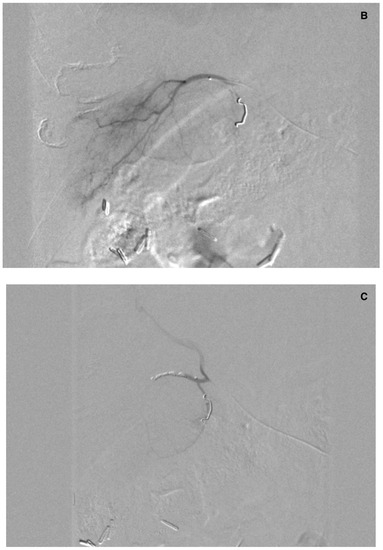

3.3. Abdominal Wall

There were three leaks through falciform arteries to the abdominal wall in 99mTc-MAA SPECT/CT. In two cases, dyna-CT confirmed their presence (Figure 5). In one case, there was no sign of contrast enhancement in the abdominal wall. These patients were not given SIRT.

Figure 6.

(A) Angiogram of the left hepatic artery showing falciform artery travelling medially beyond the margin of the liver. (B) Its presence was confirmed on Dyna-CT and showed contrast enhancement of the abdominal wall (arrows) (C), and on SPECT/CT after 99mTc-MAA injection (D) (crosshairs).